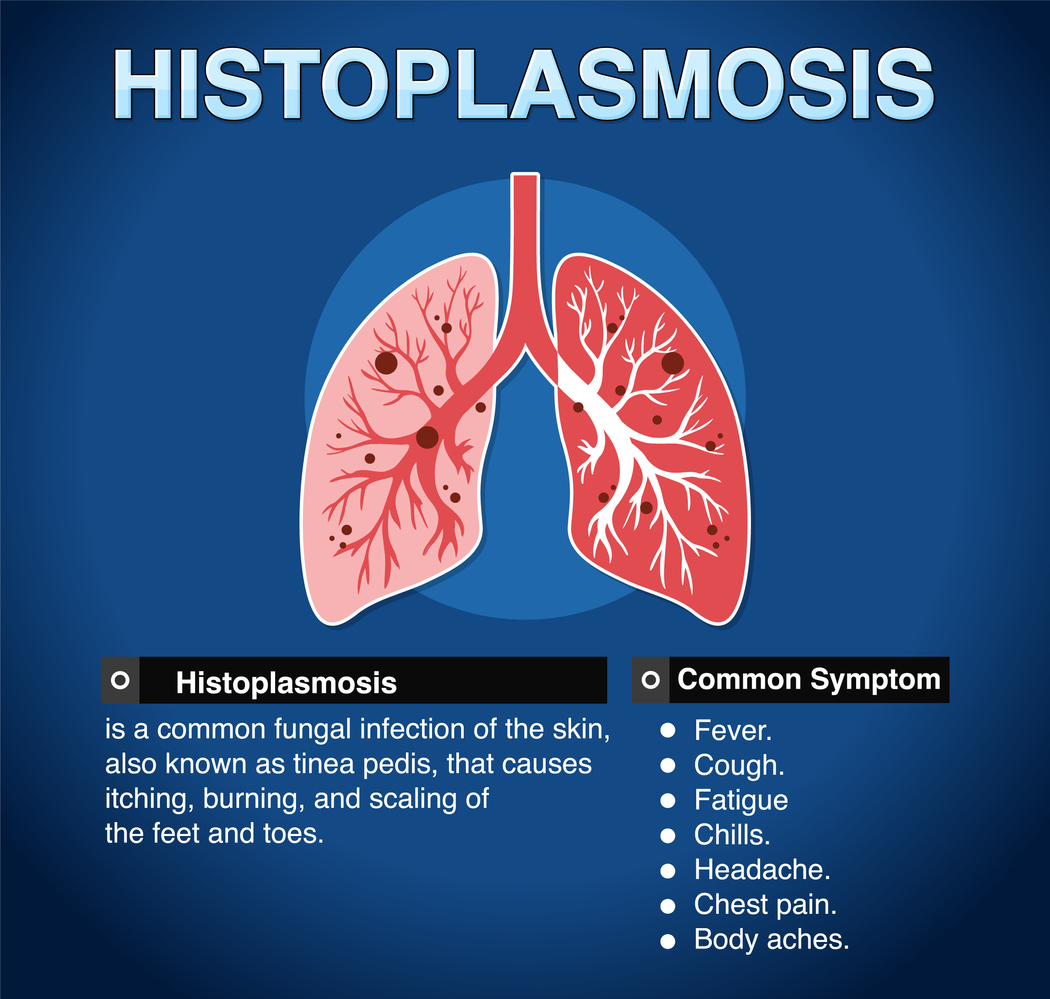

Ιστοπλάσμωση: Συμπτώματα

Οι πιο ήπιες μορφές ιστοπλάσμωσης δεν προκαλούν συμπτώματα. Όμως οι σοβαρές λοιμώξεις μπορεί να είναι απειλητικές για τη ζωή. Όταν εμφανίζονται συμπτώματα, αυτό γίνεται συνήθως μέσα σε 3-17 ημέρες μετά την έκθεση στον μύκητα και μπορεί να περιλαμβάνουν τα εξής:

- πυρετός

- κρυάδες

- πονοκέφαλος

- μυϊκοί πόνοι

- ξηρός βήχας

- πόνος στο στήθος

- κούραση

- πόνος στις αρθρώσεις

- εξάνθημα